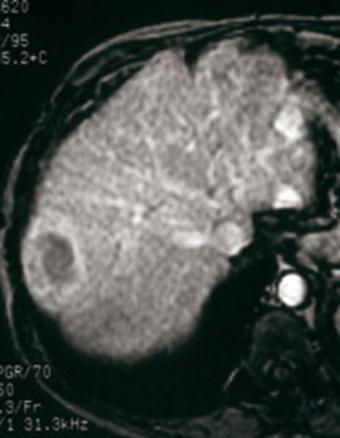

Aspect caractéristique IRM triphasique (sans injection, temps artériel = tumeur hypervasculaire, temps portal - wash out).